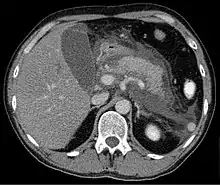

Computed tomography

Regarding the need for computed tomography, practice guidelines state:

CT is an important common initial assessment tool for acute pancreatitis. Imaging is indicated during the initial presentation if:

- the diagnosis of acute pancreatitis is uncertain

- there is abdominal distension and tenderness, fever >102, or leukocytosis

- there is a Ranson score > 3 or APACHE score > 8

- there is no improvement after 72 hours of conservative medical therapy

- there has been an acute change in status: fever, pain, or shock

CT is recommended as a delayed assessment tool in the following situations:

- acute change in status

- to determine therapeutic response after surgery or interventional radiologic procedure

- before discharge in patients with severe acute pancreatitis

CT abdomen should not be performed before the first 12 hours of onset of symptoms as early CT (<12 hours) may result in equivocal or normal findings.

CT Findings can be classified into the following categories for easy recall:

- Intrapancreatic – diffuse or segmental enlargement, edema, gas bubbles, pancreatic pseudocysts and phlegmons/abscesses (which present 4 to 6 wks after initial onset)

- Peripancreatic / extrapancreatic – irregular pancreatic outline, obliterated peripancreatic fat, retroperitoneal edema, fluid in the lessar sac, fluid in the left anterior pararenal space

- Locoregional – Gerota's fascia sign (thickening of inflamed Gerota's fascia, which becomes visible), pancreatic ascites, pleural effusion (seen on basal cuts of the pleural cavity), adynamic ileus, etc.

The principal value of CT imaging to the treating clinician is the capacity to identify devitalised areas of the pancreas which have become necrotic due to ischaemia. Pancreatic necrosis can be reliably identified by intravenous contrast-enhanced CT imaging,[18] and is of value if infection occurs and surgical or percutaneous debridement is indicated.